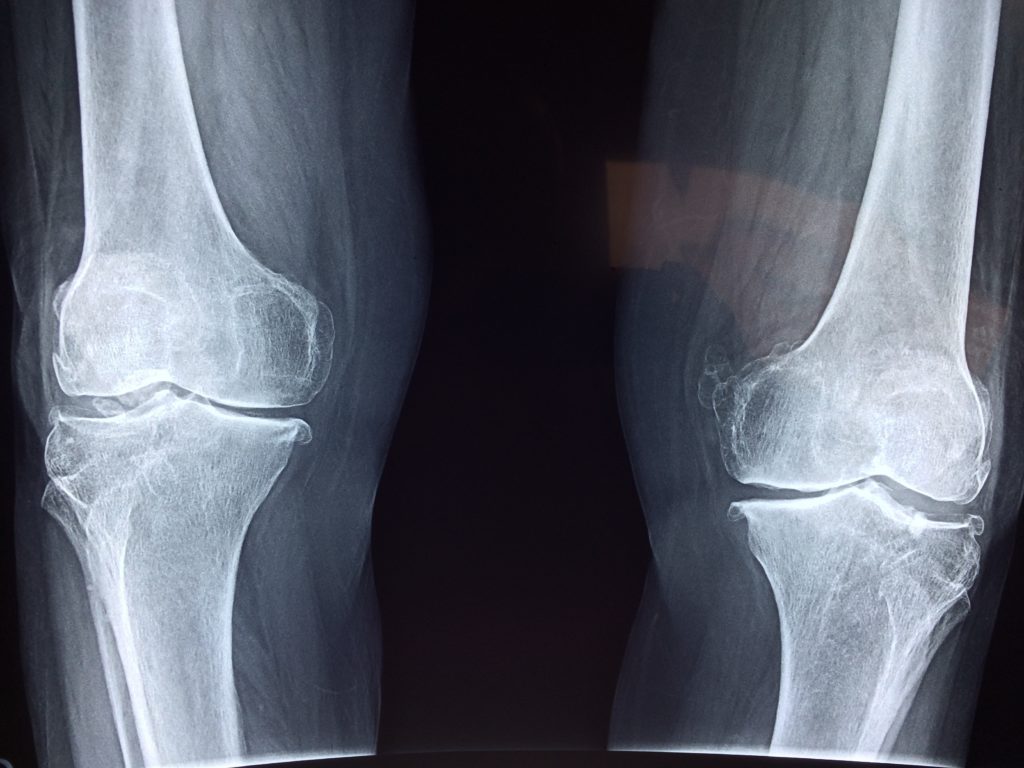

One of the most common bone diseases of all times, osteoporosis is something which makes your bones fragile and all the more prone to fractures and injuries. The word literally breaks up to mean – porous bones, or simply put, the bones that have lost most of their density and have thus become weak and hollow.

The bones in your body are made up of these complex living tissues that get generated, destroyed and regenerated all over again, all the time. As far as age is concerned, the bone mass usually only grows till the age of 30, after which it starts to decrease. Experiencing a gradual bone loss after the 30 mark is, in fact, common.

As you age, more and more bone mass tends to get lost, while our body’s rate and ability to replace that mass reduces with time. Apart from age, however, your diet and lifestyle also affect the rate at which the bones grow or lose their mass. Injuries, hereditary problems and even the prolonged use of several medications can also cause the problem of osteoporosis to surface.